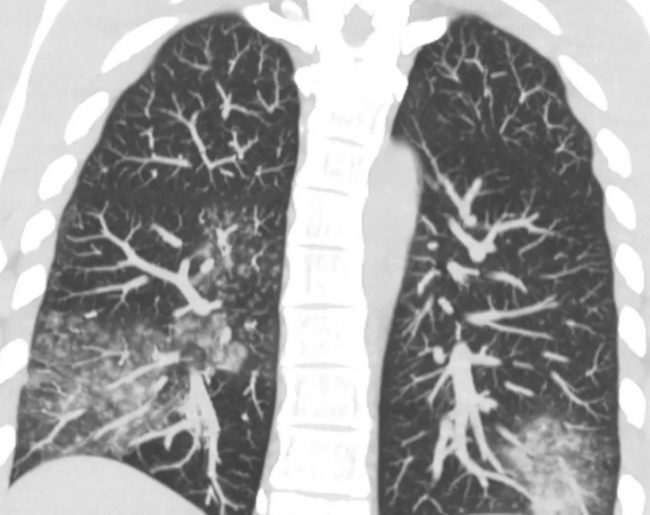

Согласно данным Центра общественного здоровья, в Украине с начала сезона зарегистрировано 13 подтвержденных случаев заражения, хотя реальное количество может быть выше. При этом в Китае больницы уже переполнены. Заражение происходит капельным путем, а инкубационный период длится от 3 до 6 дней. Заболевание может быть как легким, так и тяжелым, иногда приводит к развитию фульминантной дыхательной недостаточности, особенно у людей с ослабленным иммунитетом.

Симптомы напоминают грипп, RSV и Covid: лихорадка, головная боль, насморк и кашель. В настоящее время зафиксирован значительный рост заболеваемости. Вирус преимущественно поражает детей до 14 лет, вызывая высокий уровень госпитализаций.

Особое внимание следует уделять людям, которые находятся в группе риска, и своевременно диагностировать заболевания. В частности, врачи рекомендуют измерять уровень сатурации крови пульсоксиметром, чтобы своевременно выявить признаки дыхательной недостаточности.